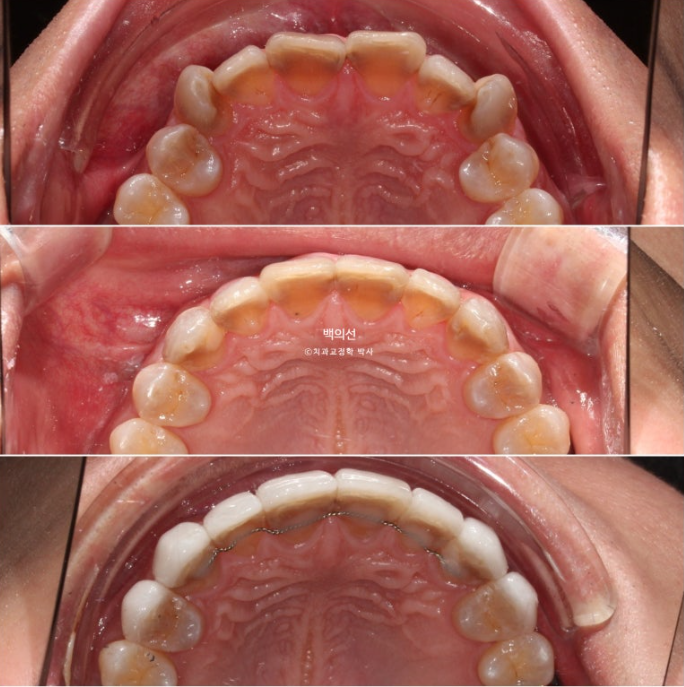

This is what the Gelami looks like on the 8 upper front teeth.

Now let’s compare the initial visit, after orthodontic treatment, and after Gelami in sequence.

This is an occlusal surface photo that gives an idea of the thickness of Gelami.

23.12~25.06